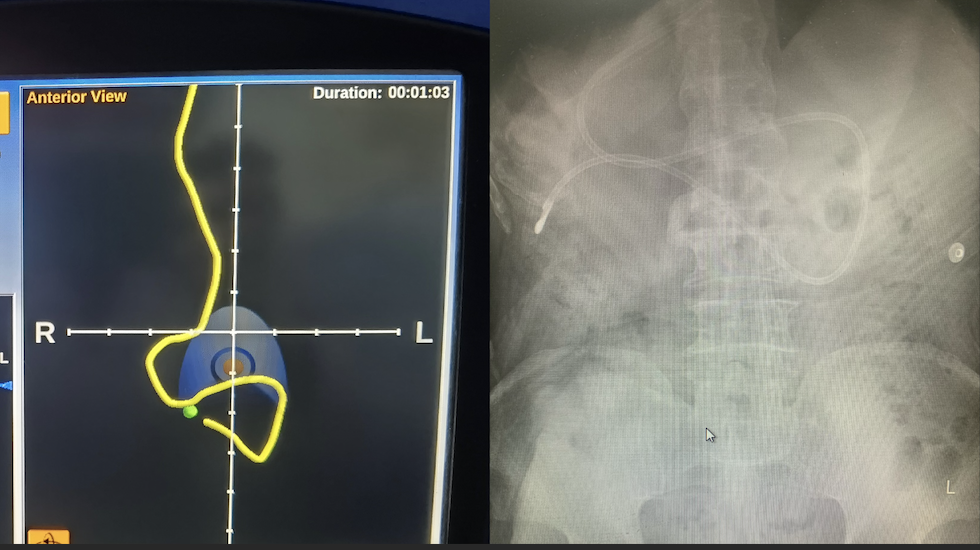

冯果医生仔细了解了患者的病情,浏览了CT图像,并向影像科郑薇医生请教阅片,反复确定胃、幽门、十二指肠的走形,当日上午便为患者在磁导航引导下置入鼻空肠管。由于准备工作充分,只花了不到10分钟便顺利将导管置入空肠段,置入深度110厘米。

鼻空肠管置管是实现幽门后喂养的一种途径,在临床尤其是在重症患者的营养支持中发挥重要作用。磁导航下的鼻空肠管置管无辐射,不受视线遮挡的影响,做到更安全,更迅速,更准确。湘雅三医院营养科在省内率先开展“磁导航下鼻空肠营养管置管术”,2022年在中南大学及湘雅三医院获得该项目的临床新技术项目立项。2023年,“徒手及联合磁导航经鼻空肠管置管术临床应用”获批“国家卫生健康技术重点推广项目”,目前已推广至省外和省内多家医院。